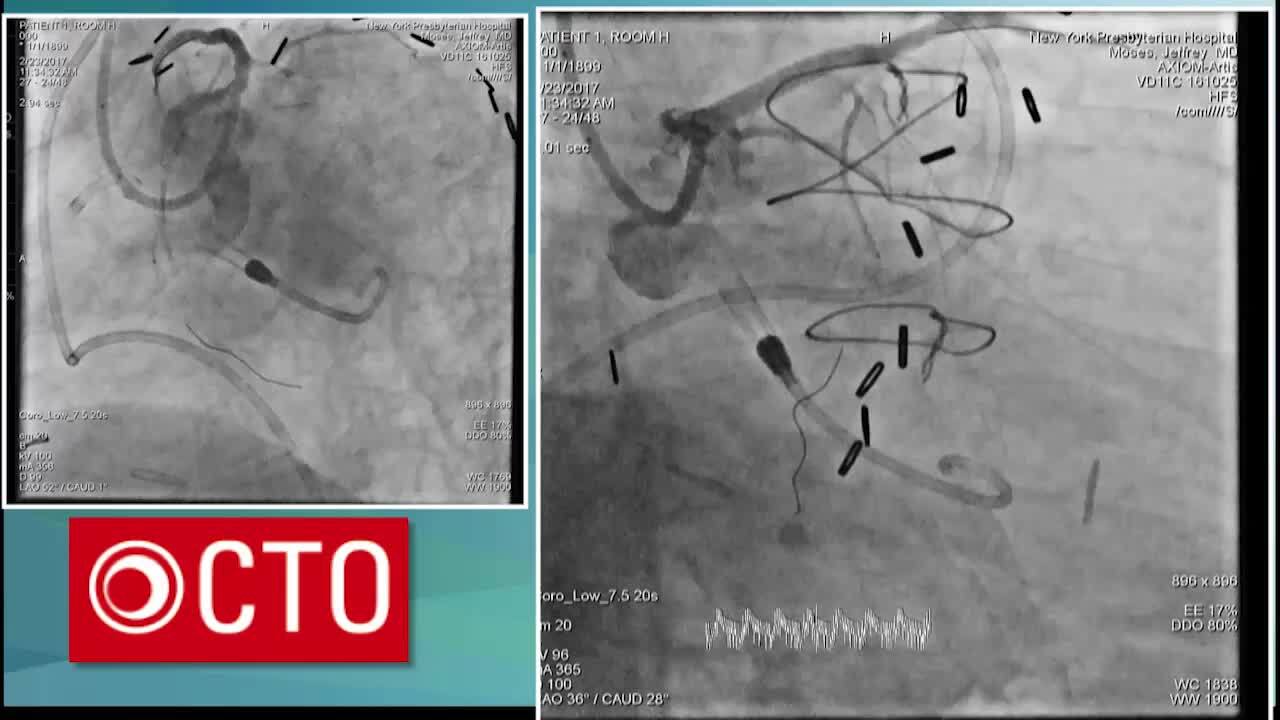

Native RCA CTO PCI in post CABG using retrograde LAD septal and rCART

February 2, 2024

» Live Case

Native RCA CTO PCI in post CABG using antegrade wiring

Video

Native LCx CTO PCI using rCART via SVG

February 3, 2024